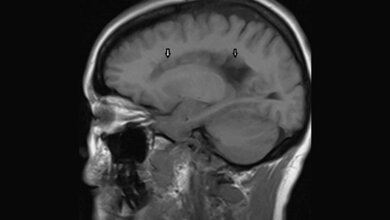

Warum sind die fehlgeleiteten Nervenzellen im Gehirn überaktiv und führen zu Entwicklungsstörungen? Wenn Nervenzellen während der Gehirnentwicklung nicht an den richtigen Ort wandern, kommt es zur sogenannten periventrikulären Heterotopie, die gut im MRT erkennbar ist. Dies ist eine Erkrankung, die oft mit medikamentenresistenten Anfällen und Lernschwierigkeiten einhergeht. Ein internationales Team um Professorin Silvia Cappello, Forschungsgruppenleiterin am Biomedizinischen Centrum der LMU und Mitglied im Exzellenzcluster SyNergy, hat nun die Eigenschaften dieser fehlplatzierten Nervenzellen untersucht und eine Erklärung für ihre Hyperaktivität gefunden.